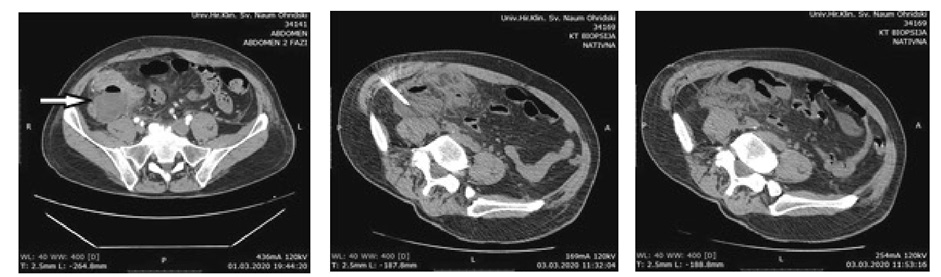

Two patients presented with postoperative pyrexia without the need of any additional intervention. There were no cases of wound infection. One patient was reoperated for early postoperative mechanical bowel obstruction and had uneventful postoperative period. One patient presented with postoperative IAA and it was successfully evacuated and drained by CT guidance (Figure 1).

The IAA treatment can be operative (laparotomy) or with US or CT-guided percutaneous drainage. The minimal invasiveness of the procedure, its efficiency (over 90% successfulness) and no need for general anesthesia, makes the percutaneous drainage first choice method for post appendectomy IAA. However, it has some limitations when a diffuse interintestinal collections are present [36–38].